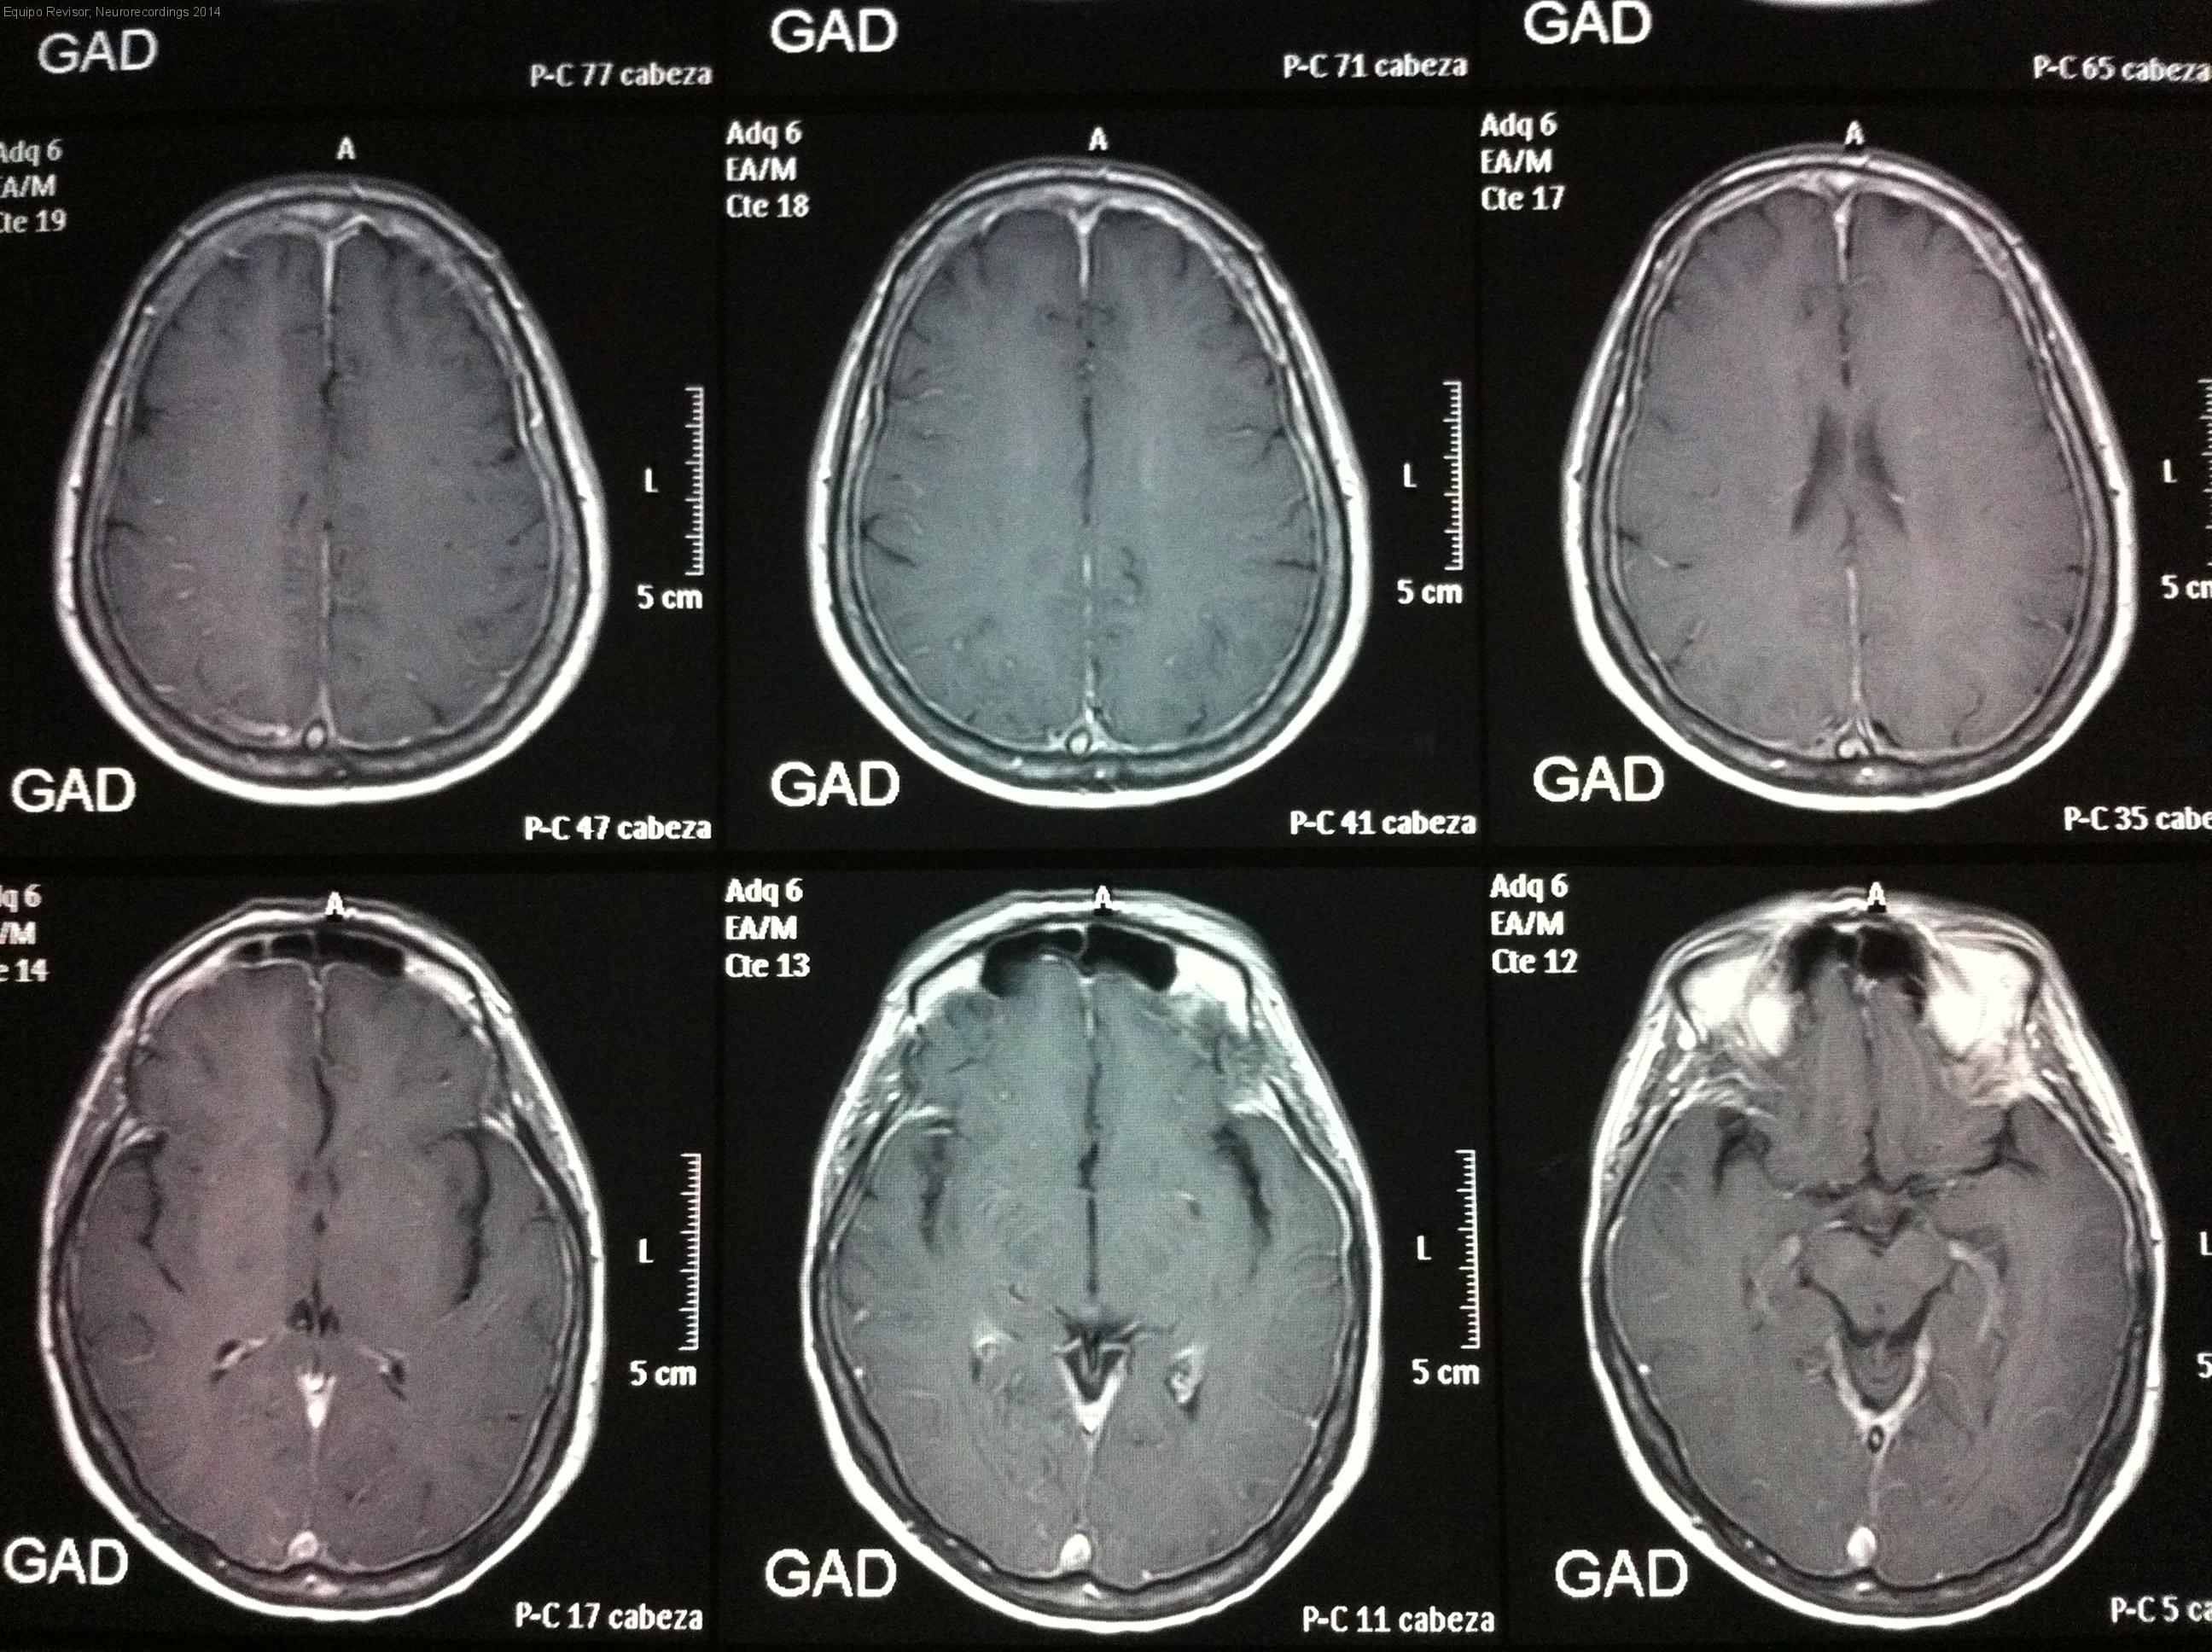

Mujer | 40 años

Diagnóstico final: Hipotensión licuoral

Neurología: Cefalea

Etiología: Miscelánea